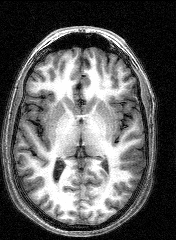

The last session involved several MRI and fMRI scans while completing tasks in the noisy environment of the scanner. Thanks to a friend who worked at the Institute, I was able to secure a copy of the raw data and an application to turn it into images, some of which are displayed here.

The images to the right are virtual 'slices', taken horizontally, starting from the top and working down. Cerebrospinal fluid is dark, the white matter appears light.